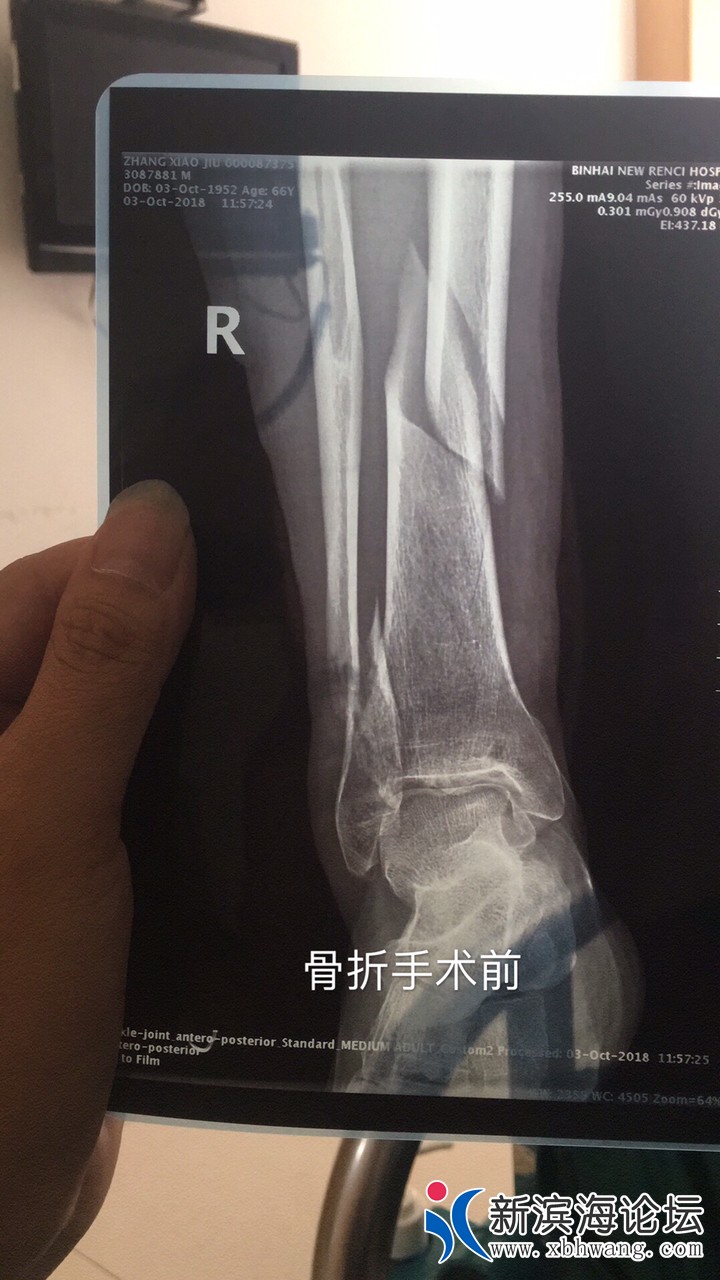

曝光滨海中医院无医德的骨科副主任孟俊柏害我父亲二次手术

中医院骨科副主任孟俊柏,可能术前没有收到红包,10月6日把我父亲的骨折手术做失败了,造成医疗事故,害得我父亲10月8日下午4:30手术结束后一直疼痛难忍,吃了好多止疼药,和塞肛门的止疼药,一直到凌晨四点才入睡,12个小时非常人能忍受的痛苦,10月8日拍片复查,拍片时被我发现手术失败,去找孟俊柏讨说法,他不面对现实,和科室的医生还忽悠我说,这个手术没有问题,骨头可以长好,睁眼说瞎话,大骨头都戳到小骨头了,怎么可能长好,长好也会残废,这样无医德的医生,漠视患者的身体健康权益,一点医德都没有,被我投诉到骨科主任顾春生处,顾春生一看片子,承认有问题,电话叫来科室的医生,医生还是睁眼说瞎话说没什么问题,我问他们,如果你的亲人骨折了,手术做成这样了,你认可吗?两个人屁都不放,顾春生主任说肯定要二次手术,准备明天上午二次手术,后来无徳庸医孟俊柏发微信给我说,骨折复位有一定的标准,和我们想(像)信的不一样,难道他的手术标准是比没手术还差吗?我回复说,不要跟我解释,我无法接受,他跑到病房里说,没事的,明天上午帮你调整一下,把针线拆开,把口子重新划开一下,半个小时调整好了,说现在手术后和没做手术差不多,我说那我为什么要花钱做手术,这样的话也说得出口,说的和玩的一样,我说NM的你以为是修车吗,随便调整一下,被我骂的灰溜溜走了,气得我立刻去院长那里投诉!这种人没有医德的东西怎么能混到骨科副主任,各位网友如果有亲人朋友不幸骨折,如果去了中医院,千万不要找孟俊柏这个无医德的人,希望各位帮我转发到朋友圈,微信群,曝光滨海县中医院骨科这种无医德,不负责任,漠视患者健康权益的医生。